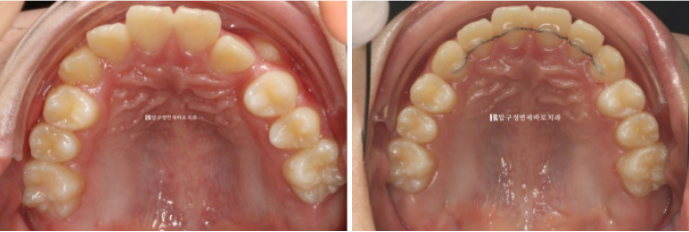

처음과 끝

악궁이 약간 찌그러져 있었지만 배열 후 좋아졌습니다.